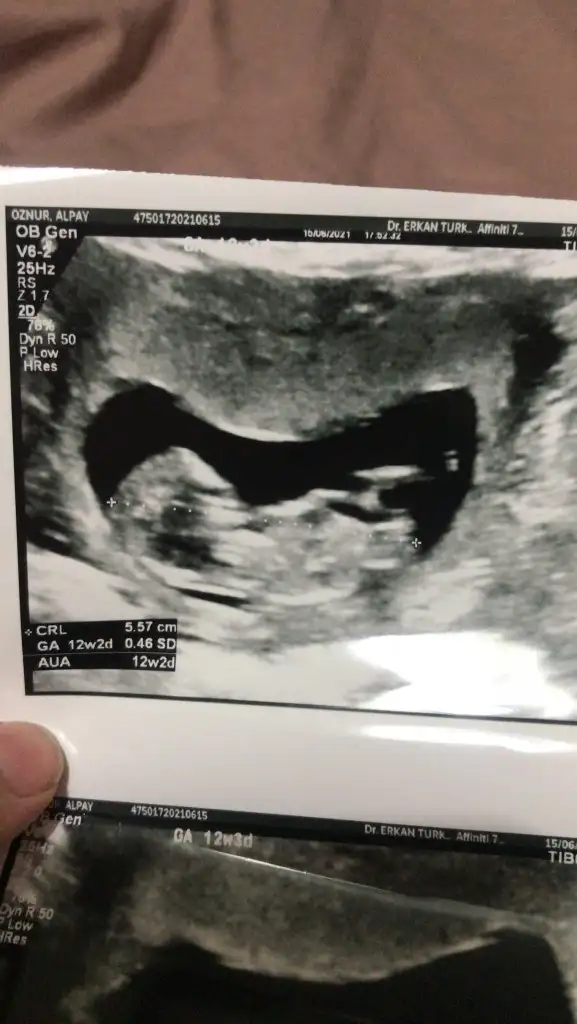

Bana da cinaiyet tahmini yapar mısınız ilk resim 6. Hafta vajinal ultrason 2. Resim 12+3

Eklentiler

• 7635E279-AE4F-4448-A29E-F5EE0F5EC816.webp

7635E279-AE4F-4448-A29E-F5EE0F5EC816.webp

15,2 KB · Görüntüleme: 94

• A891C580-E3C5-4568-B829-9AC8ADB4170A.webp

A891C580-E3C5-4568-B829-9AC8ADB4170A.webp

28,4 KB · Görüntüleme: 77